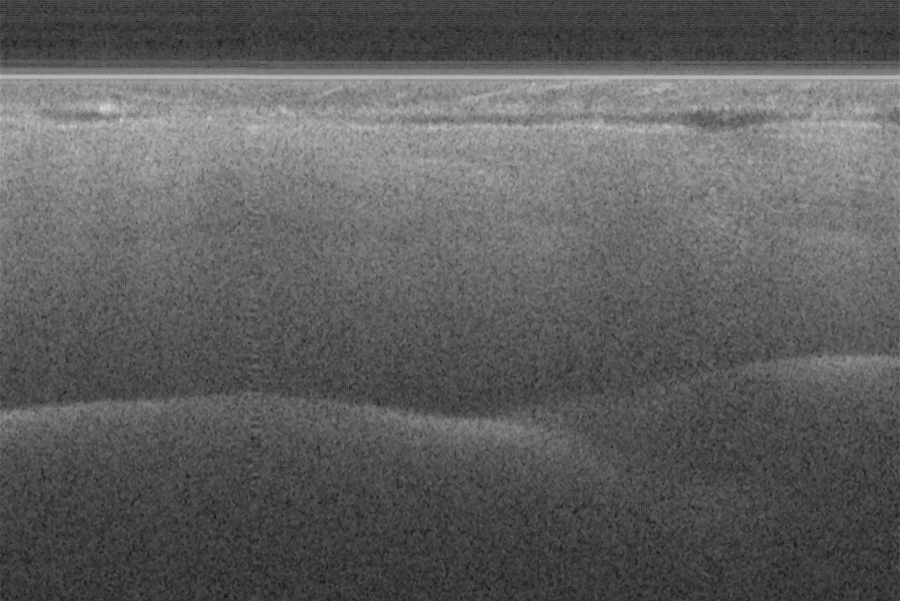

Fig. 16 (a) and (d) show SS-OCT images of human finger in vivo taken using fiber probes #

14 (working distance, depth of field and spot diameter of 1.2 mm 1.1 mm, and 27 m) and #

16 (working distance, depth of field and spot diameter of 0.9 mm 0.33 mm, and 16 m)

acquired by our catheter-based complex SS-OCT using our 3x3 Mach-Zehnder

interferometer with unbalanced differential detection technique with image size of 5x2mm.

The image depth shown in Fig. 16 (a) is slightly larger than that in Fig. 16 (b), but the image

is blurrier in Fig. 16 (a) than that in Fig. 16 (b), which taken by the probe with larger depth of

field and spot size. The image shown in Fig. 16 (b) has higher resolution than that in Fig. 16

(a), which can be seen clearly with finer structures in layer of epidermis (grey arrow), sweat

gland (white arrow), and blood vessel in subcutis layer (black arrow).